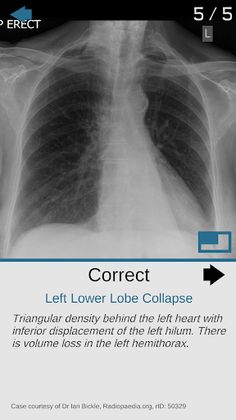

Test yourself on basic x-ray interpretation, tracking your strengths and weaknesses as you go.